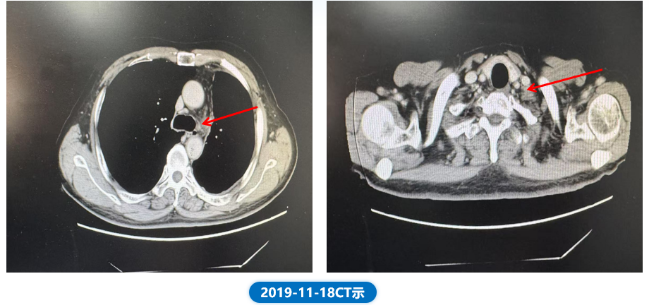

• 2019.11.18 复查CT,与前颅脑及胸腹CT比较,左下肺病灶较前相似,右肺及右侧叶间胸膜多发小结节,部分较前略缩小,左肺门,纵隔及左侧心膈角见多发肿大淋巴结教前整体缩小;左锁骨上淋巴结较前略增大;部分骨转移硬化较前稍明显。

肺“长”实“例” :从真实世界病例看EGFR ex20ins NSCLC患者综合治疗模式下的长生存漫漫路1678.png